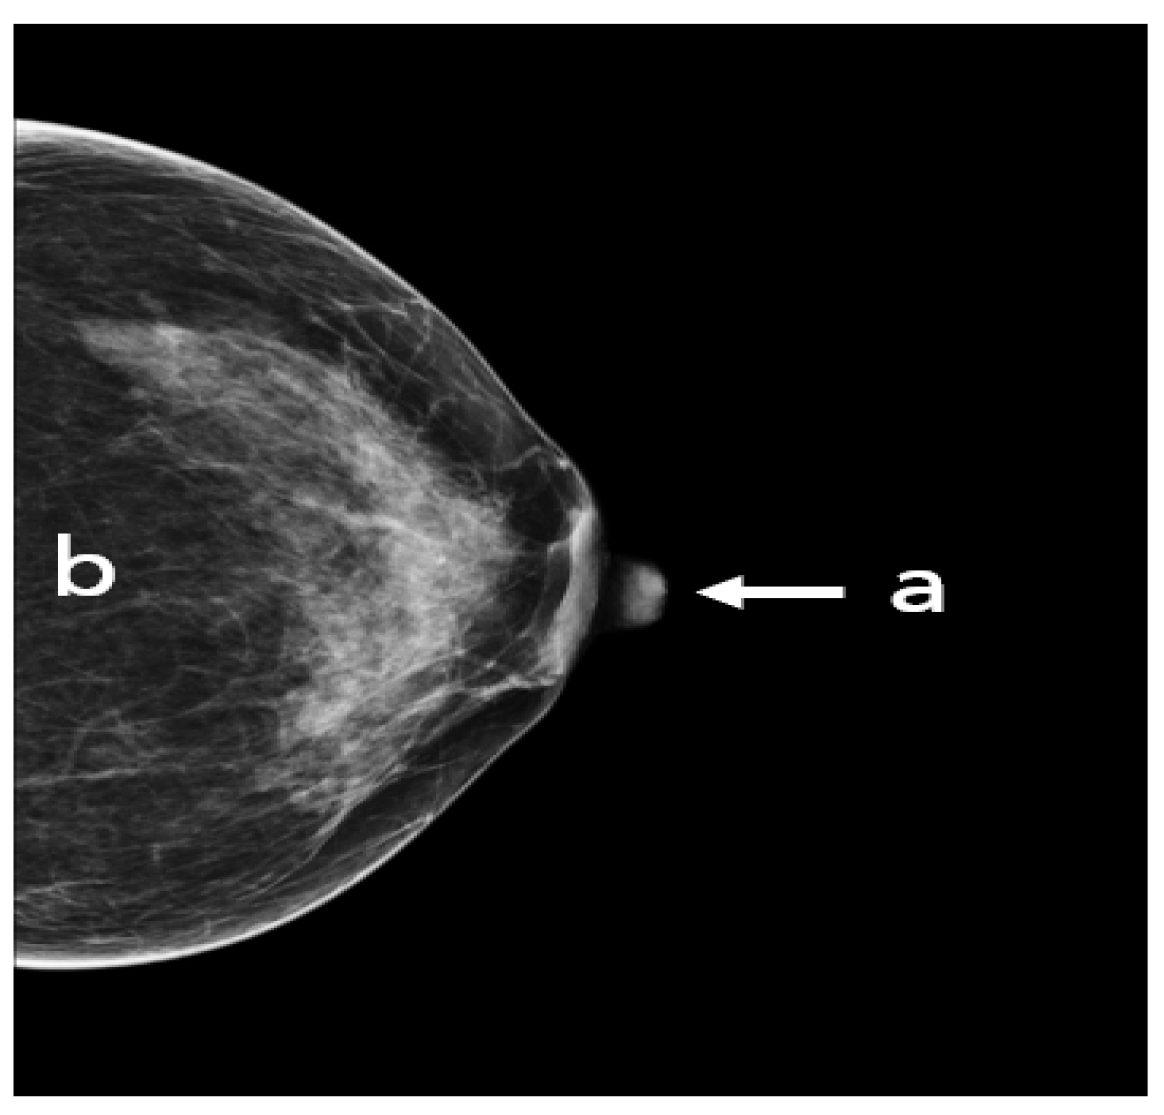

3.5. CC: Nipple Position